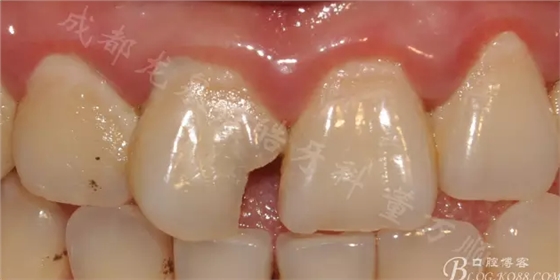

一個(gè)漂亮的女孩 17歲

常規(guī)口內(nèi)檢查可見(jiàn) 口腔衛(wèi)生差 前牙齲壞 自述早上冷水刷牙會(huì)有不適(磨牙基本上都有齲壞)

主要先解決前牙美觀問(wèn)題 12 21鄰面均有齲壞